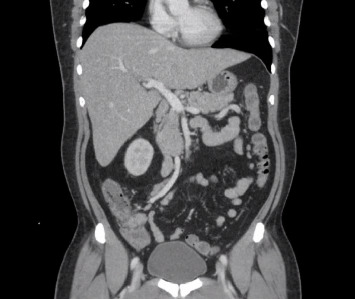

背景:伤寒是一种由伤寒沙门菌和副伤寒沙门菌引起的多系统疾病,可通过受污染的水和食物经粪便经口传播。在美国,这是一种罕见的诊断,大多数病例报告发生在返回的旅行者身上。肝炎和胆汁淤积是沙门氏菌感染的罕见后遗症。然而,急性肝衰竭(ALF)是非常罕见的。我们报告一例伤寒在返回旅行者到美国进展到ALF。病例介绍:一名48岁男性,表现为高热、腹痛、呕吐、胆汁性便、尿色深、皮肤和巩膜变黄,持续一周。他对甲型和乙型肝炎有免疫力,近期用药也没有变化。他没有饮酒史。就诊时,患者心动过速,但血流灌注良好,伴有弥漫性腹部压痛。实验室结果显示白细胞增多,肌酐升高,肝酶升高的混合肝细胞和胆汁淤积模式,氨水平升高,溶血参数阴性。病毒性、自身免疫性和代谢性肝炎均为阴性。腹部超声显示胆道系统正常,腹部CT显示多发肝囊肿,肠系膜及肝门淋巴结病变,回肠末端轻度增厚。开始静脉注射头孢曲松和甲硝唑。血液培养培养出伤寒沙门氏菌。患者临床病情恶化,出现精神状态改变、呼吸窘迫,终末期肝病(MELD)评分呈上升趋势,并被升级至重症监护病房。开始静脉滴注美罗培南,临床恢复,重复血培养阴性。患者完成2周美罗培南治疗后出院。结论:伤寒可引起危及生命的肝功能衰竭,但罕见。临床医生应该意识到这一点,因为它的进展迅速,临床病程危及生命,而且耐多药和广泛耐药伤寒的增加导致开始使用正确抗生素的延误。

Background: Typhoid fever is a multisystemic illness caused by Salmonella typhi and Salmonella paratyphi, transmitted fecal orally through contaminated water and food. It is a rare diagnosis in the US, with most cases reported in returning travelers. Hepatitis and cholestasis are rare sequelae of salmonella infection. However, acute liver failure (ALF) is exceptionally uncommon. We report a case of typhoid fever in a returning traveler to the US progressing to ALF. Case Presentation: A 48-year-old man presented with high-grade fever, abdominal pain, vomiting, acholic stools, dark urine, and yellowish discoloration of skin and sclera for one week. He was immune to hepatitis A and B, with no recent change in medications. He had no history of alcohol consumption. On presentation, the patient was tachycardic but well perfused with diffuse abdominal tenderness. Laboratory results showed leukocytosis, elevated creatinine, mixed hepatocellular and cholestatic pattern of raised liver enzymes, elevated ammonia levels, and negative hemolytic parameters. Viral, autoimmune, and metabolic causes of hepatitis were negative. Ultrasound of the abdomen revealed a normal biliary system and a computerized tomography (CT) scan of the abdomen showed multiple liver cysts, mesenteric and porta-hepatis lymphadenopathy, and mild thickening of the terminal ileum. Intravenous (IV) ceftriaxone and metronidazole were initiated. Blood cultures grew S. typhi. The patient clinically deteriorated and developed altered mental status, respiratory distress, and an up-trending Model for End-Stage Liver Disease (MELD) score and was upgraded to the intensive care unit. IV meropenem was initiated, resulting in clinical recovery and negative repeat blood cultures. The patient completed 2 weeks of meropenem and was discharged. Conclusion: Typhoid fever can cause life-threatening liver failure which is rare. Clinicians should be aware of this due to the rapid progression and life-threatening clinical course, as well as the rise of multidrug-resistant and extensively drug-resistant typhoid causing delays in starting the right antibiotic.